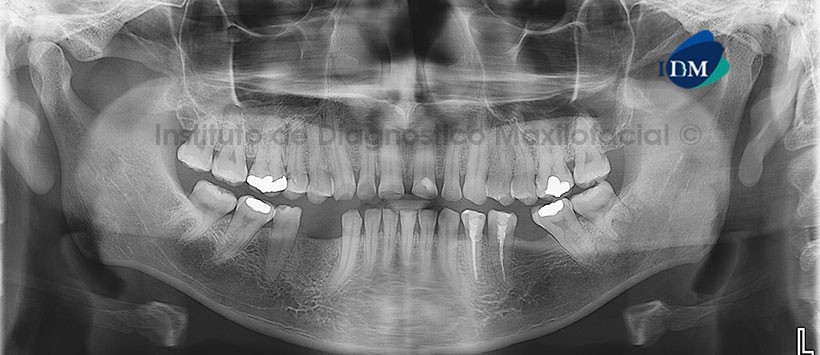

En la radiografía panorámica (Figura 1) se aprecia rarefacción ósea a nivel de la pieza 3.8, donde también se observa borramiento de corticales de las láminas duras y del conducto dentario inferior en ese lado.